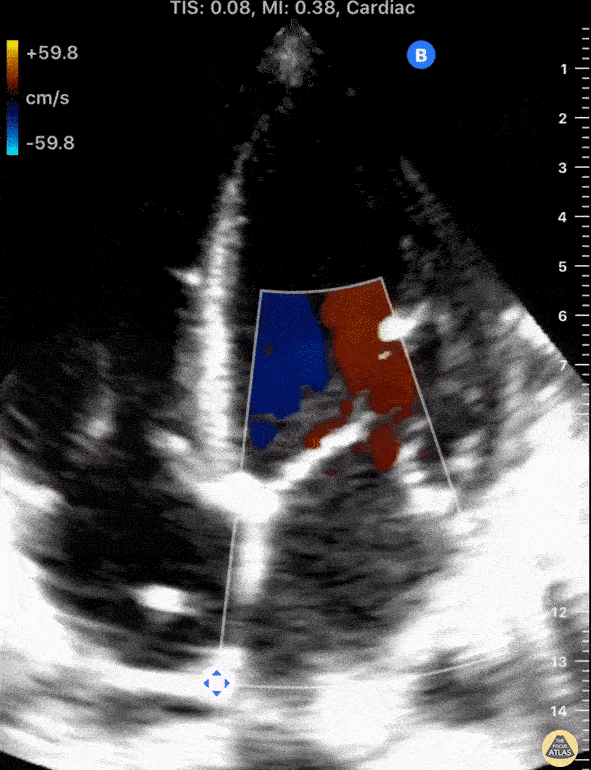

A 58-year-old male with ischemic cardiomyopathy and recently implanted AICD presented with subacute dyspnea without signs of volume overload on physical exam. Seen here is POCUS (apical four chamber view) notable for mitral valve regurgitation (MR) as demonstrated by the presence of a regurgitant jet. After excluding acute myocardial ischemia, patient was diagnosed with secondary (functional) MR due to heart failure. Separately, notice the hyperechoic lesion traversing the right atrium. In this patient it represents a segment of his AICD. The differential diagnosis, however, includes atrial thrombus and/or vegetation. Shahad Al Chalaby, MD. PGY3 Internal Medicine Highland Hospital. Alemeda Health System Internal Medicine Residency Program. CA, USA @shahad_Chalaby